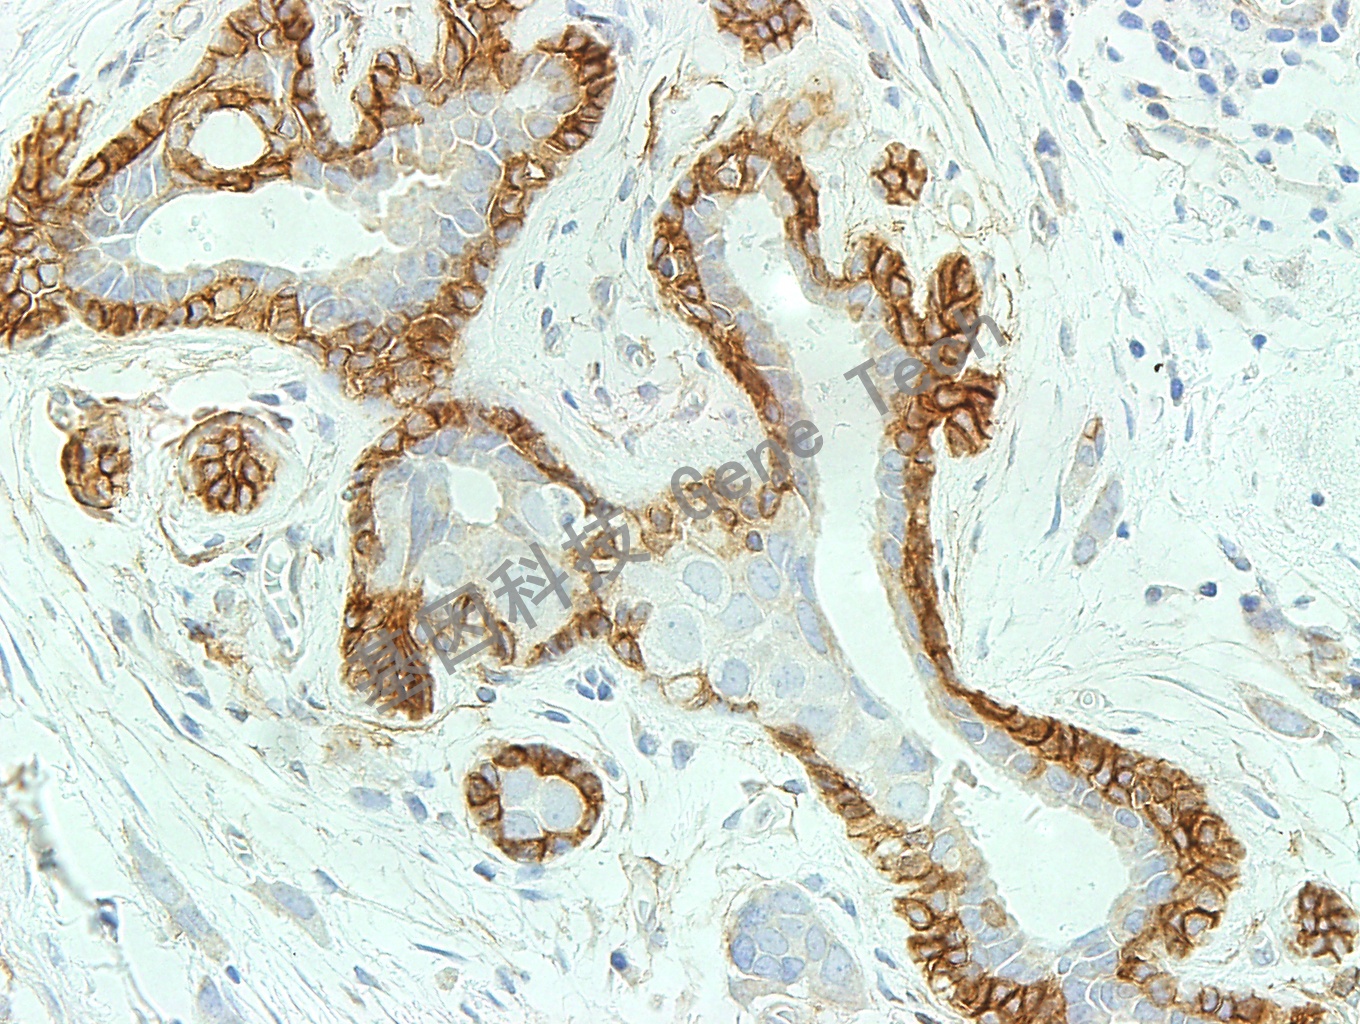

| 乳腺癌石蠟切片,用 NGFR(GT2258)染色,細(xì)胞漿陽性,DAB 顯色。 | ||

| 預(yù)處理:高pH熱修復(fù) | 陽性部位:細(xì)胞漿 | 陽性對照:乳腺組織 |

| 簡介:NGFR(nervegrowthfactorreceptor,神經(jīng)生長因子受體)是一種分子量約為75kDa的糖蛋白,又名P-75NTR。該受體蛋白是頭一個被分離獲得的神經(jīng)營養(yǎng)蛋白受體,屬于腫瘤壞死因子(TNF)受體家族,主要表達(dá)于交感與感覺神經(jīng)元,其次在各種神經(jīng)脊細(xì)胞或者來源于該類細(xì)胞的腫瘤細(xì)胞(如:黑色素瘤、惡性黑色素瘤、神經(jīng)母細(xì)胞瘤、嗜鉻細(xì)胞瘤、纖維神經(jīng)瘤、神經(jīng)侵犯性痣)中有表達(dá)。研究都表明NGFR是促結(jié)締組織增生性和嗜神經(jīng)性黑色素瘤的可靠性標(biāo)記物。利用NGFR抗體可標(biāo)記乳腺導(dǎo)管的肌上皮細(xì)胞與小葉內(nèi)成纖維細(xì)胞,有助于判斷乳腺病變的良惡性質(zhì)。 | ||